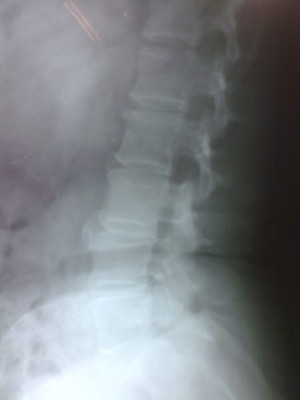

Radiografías con enfoque en fisiatría

Envíado por Dr. Hernán Darío Sánchez Ramos